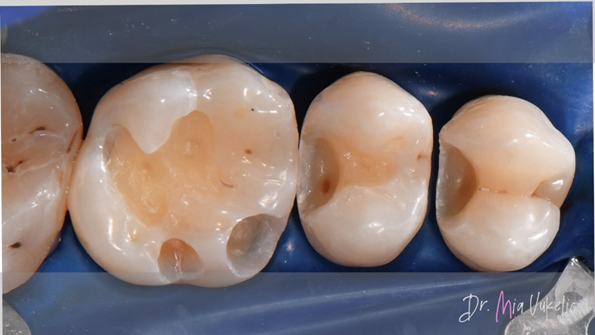

Die Zähne wurden mit Hilfe von Kofferdam und Keilen sorgfältig isoliert. Für die Kavitätenpräparation kam zu Beginn ein zylindrischer Bohrer zum Einsatz. Nach der Entfernung der Restauration wurde das demineralisierte Dentin mit einem Stahlbohrer entfernt. Zum Abschluss der Kavitätenpräparation wurden konvergente Wände in divergente Wände umgearbeitet und die Kavitätenoberfläche mit Diamantpolierern poliert.